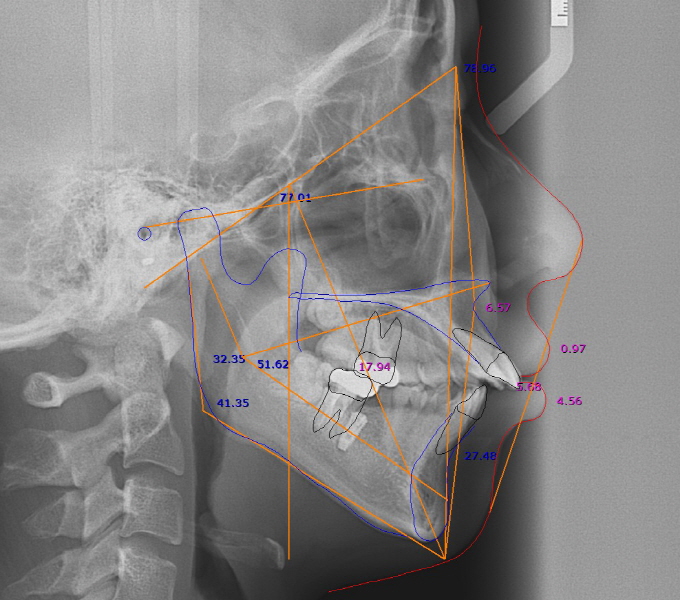

| Fig. 2: 62¼¼ ¿©ÀÚ, Àå±â°£ Ä¡ÁÖ±³Á¤Ä¡·á¸¦ ¸¶ÃÆ°í º¸Ã¶Ä¡·á¿Í ÀÓÇöõƮġ·á±îÁö ÀüºÎ ¿Ï¼ºÇÏ¿´´Ù. |